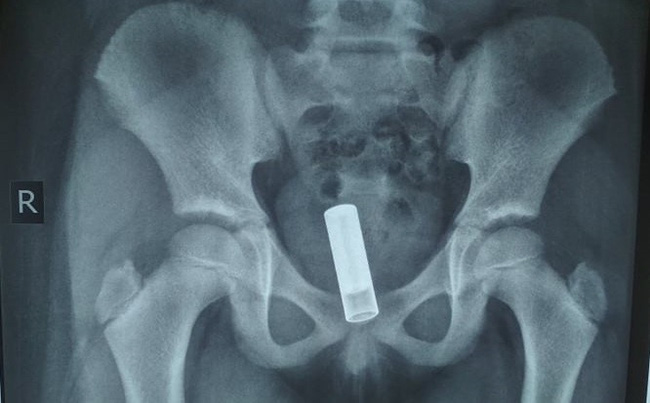

Kết quả siêu âm ghi nhận: Bóng cản âm trong lòng âm đạo, kích thước16x30mm. Theo dõi dị vật âm đạo.

Hình ảnh chụp X-quang bụng không sửa soạn